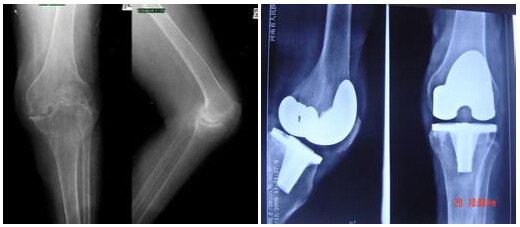

(圖:急性風(fēng)濕性關(guān)節(jié)炎治療前后x片)